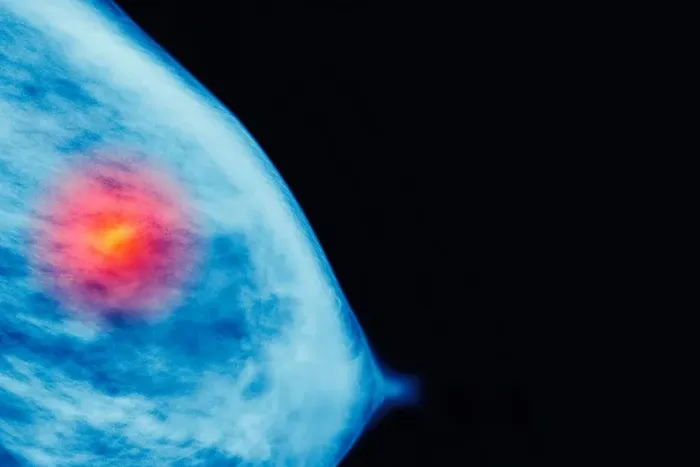

En coincidencia con el Día Mundial de Lucha contra el Cáncer de Mama, desde el Hospital de Clínicas de Buenos Aires destacaron que si bien el autoexamen es recomendado para detectar alteraciones en las mamas, los especialistas hablan de un periodo ventana de nueve años desde el momento de una mutación a nivel celular hasta que se hace una tumoración clínicamente palpable.

En sus primeras etapas, el índice de recuperación de la enfermedad es del 97%, por lo que el diagnóstico precoz aumenta mucho las posibilidades de curarlo.

“El cáncer de mama es el cáncer más frecuente en nuestro país, con 21.000 casos nuevos por año, y la primera causa de muerte por cáncer en la mujer con 6.400 muertes por año. El riesgo de padecer cáncer de mama de una mujer a lo largo de su vida es de 13%”, resaltó el médico mastólogo de la División Cirugía Oncológica del Hospital de Clínicas, Sebastián Alba Posse, sobre la estadística que señala que una de cada ocho mujeres desarrollará la enfermedad a lo largo de su vida. “La mayoría de estos casos son de origen esporádicos y un porcentaje mucho menor tiene antecedentes heredofamiliares o genéticos que lo puedan predisponer a la enfermedad, es importante controlarse en ambos casos”, agregó.

“Es muy importante que la mujer aprenda a conocer sus mamas, como lo es estar atentas a la aparición de nódulos, derrames de sangre por pezón, retracción de la piel o cualquier otro signo fuera de lo común -sostuviAlba Posse-. Pero no es el autoexamen mamario el diagnóstico precoz por excelencia. Las lesiones palpables suelen tener al menos un centímetro de diámetro, el beneficio de los estudios de screening o tamizaje como la mamografía es detectar estos tumores en etapa subclínica, siendo la posibilidad de curación más alta. En caso de aparición inesperada de un nódulo palpable, es importante no perder la calma y recurrir al profesional para su estudio y control”.